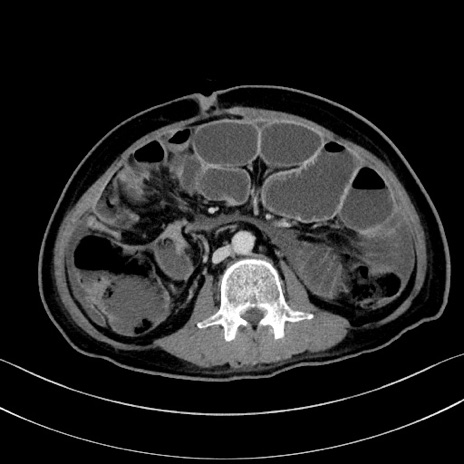

冠状断像

【症例】60歳代男性

【主訴】嘔吐

【現病歴】胃癌にて胃全摘後。食思不振が悪化し、夜中に嘔吐することがある。

【既往歴】胃癌、胃全摘、脾摘、胆摘後

【データ】WBC 5900、CRP 10.56